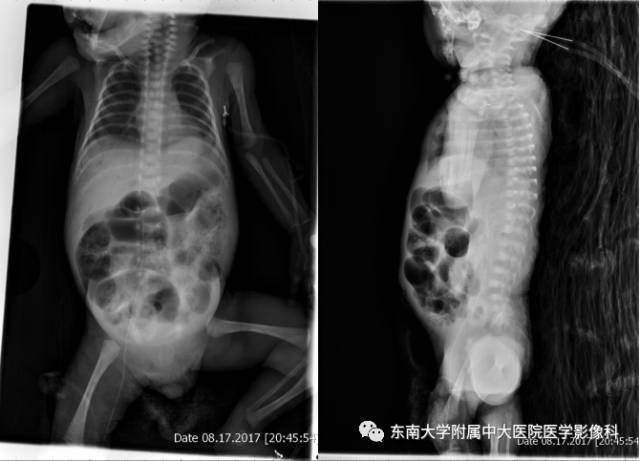

病史

因“胎龄28 2周,生后呼吸急促、反应差1小时”入院。因“胎膜早破”顺产出生于本院,入院约20天后出现腹胀呕吐。

X线